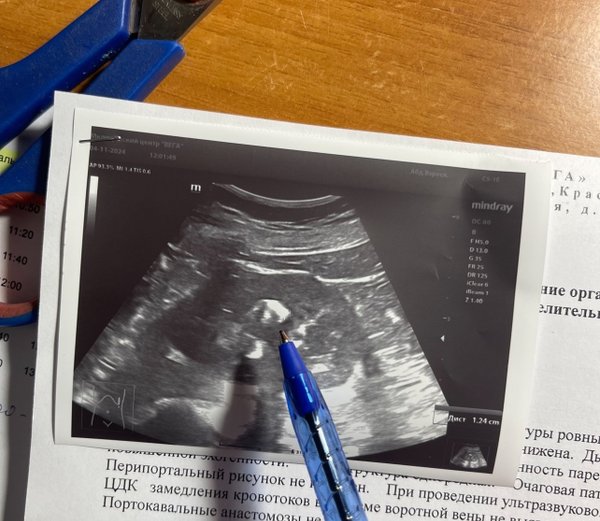

Бородулина Наталья (Врач УЗИ, Косметология) (14.01.2026): #Асцит – патологическое состояние, при котором в ️брюшной полости (животе) начинает скапливаться жидкость. Самой частой причиной является #цирроз печени (до 90% всех выявляемых асцитов), вторым по частоте #онкологический асцит. ‼️Для диагностики необходим осмотр врача и #ультразвуковое исследование. ️Симптомы асцита: -Увеличение живота в объеме; -Одышка; -Реже — боль (за счет растяжения брюшной стенки). Что показывает УЗИ при асците: Подтверждает факт наличия свободной жидкости. Оп… — Читать дальше

ределяет точный объем — даже небольшое количество (от 100 мл!). Находит причину — часто видит изменения в печени, почках, поджелудочной железе, опухоли. Контролирует лечение — помогает отслеживать, уходит ли жидкость. Безопасно и направляет — без боли и излучения, а главное — показывает врачу, куда двигаться дальше для вашего эффективного лечения. Не стоит гадать и ждать. Своевременная диагностика — это ключ к правильной тактике лечения и улучшению качества жизни ️ Доверьте свое здоровье профессионалам и современной диагностике. ️ Запишитесь на УЗИ #экспертного класса ‼️нажмите «Записаться» или позвоните нам

#Асцит – патологическое состояние, при котором в ️брюшной полости (животе) начинает скапливаться жидкость. Самой частой причиной является #цирроз печени (до 90% всех выявляемых асцитов), вторым по частоте #онкологический асцит.

‼️Для диагностики необходим осмотр врача и #ультразвуковое исследование. ️Симптомы асцита:

-Увеличение живота в объеме; -Одышка; -Реже — боль (за счет растяжения брюшной стенки).

Что показывает УЗИ при асците:

Подтверждает факт наличия свободной жидкости.

Оп… — Читать дальше

Находит причину — часто видит изменения в печени, почках, поджелудочной железе, опухоли.

Контролирует лечение — помогает отслеживать, уходит ли жидкость.

Безопасно и направляет — без боли и излучения, а главное — показывает врачу, куда двигаться дальше для вашего эффективного лечения.